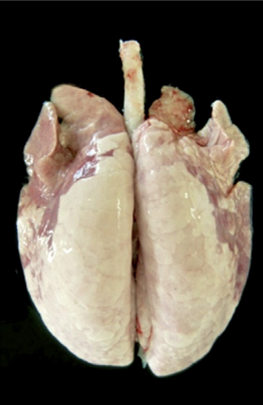

The presence of the infection is usually confirmed by M.hyo specific seroconversion or by the detection of germs by PCR in the laryngeal swabs (Pieters et al. 2017, Sibila et al. 2009). Lung tissue infected with M.hyo develops consolidation and catarrhal broncho-pneumonia with purple to grey regions of meaty aspect. The consolidation can be observed from 3-12 weeks post infection. The lesions are mainly localized in the apical and cardiac lobes, as well as in the anterior part of the diaphragmatic lobes and in the intermediate lobe. Lesions resolve after 12 to 14 weeks with formation of interlobular fissures (Maes et al. 2008). Considering the chronic type of such lesions, bronchopneumonia with the cranioventral consolidation of lungs is very indicative for EP also in slaughter pigs.

Example of a lung with lesions derived from an experimental M.hyo inoculation (Garcıa-Morante, 2016).